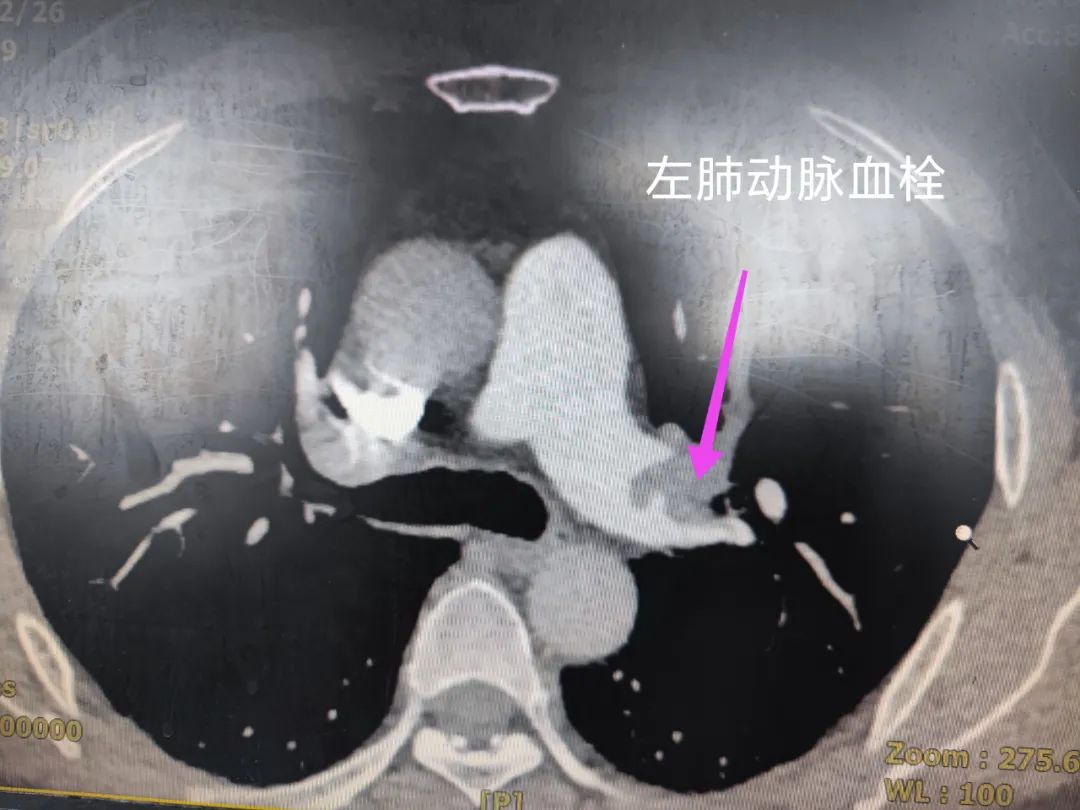

肺栓塞是三大致死性胸痛之一,往往继发于骨折、外科手术后、长期卧床、妊娠等情况。

第三例患者为中年男性,长期锻炼,身体素质良好,无基础疾病。起因于入院前半月下蹲给宠物洗澡时间较长,随之出现右下肢膝盖以下肿胀,未行诊治;于入院前 1 天出现气短、胸闷。虽然心电图和其他初步临床资料不典型,但医院急诊科同仁果断行肺动脉 CTA 明确双侧肺动脉栓塞。

经心血管病医院及时植入下腔静脉滤器后溶栓及强化抗凝治疗,病情明显好转。由初始吸氧状态下指脉氧 86%,改善为非吸氧时 97%,气短、胸闷及右下肢肿胀消除。以上三例病例均为心血管病科日常诊疗活动中常见疾病,轻微的表象下却隐藏着巨大的隐患。因此,患者在出现身体、疾病异常的现象和标准治疗收效不佳时,往往可以追踪到实质的病因,及时采取有效治疗可以降低疾病风险,使患者生存质量提高,预后改善。